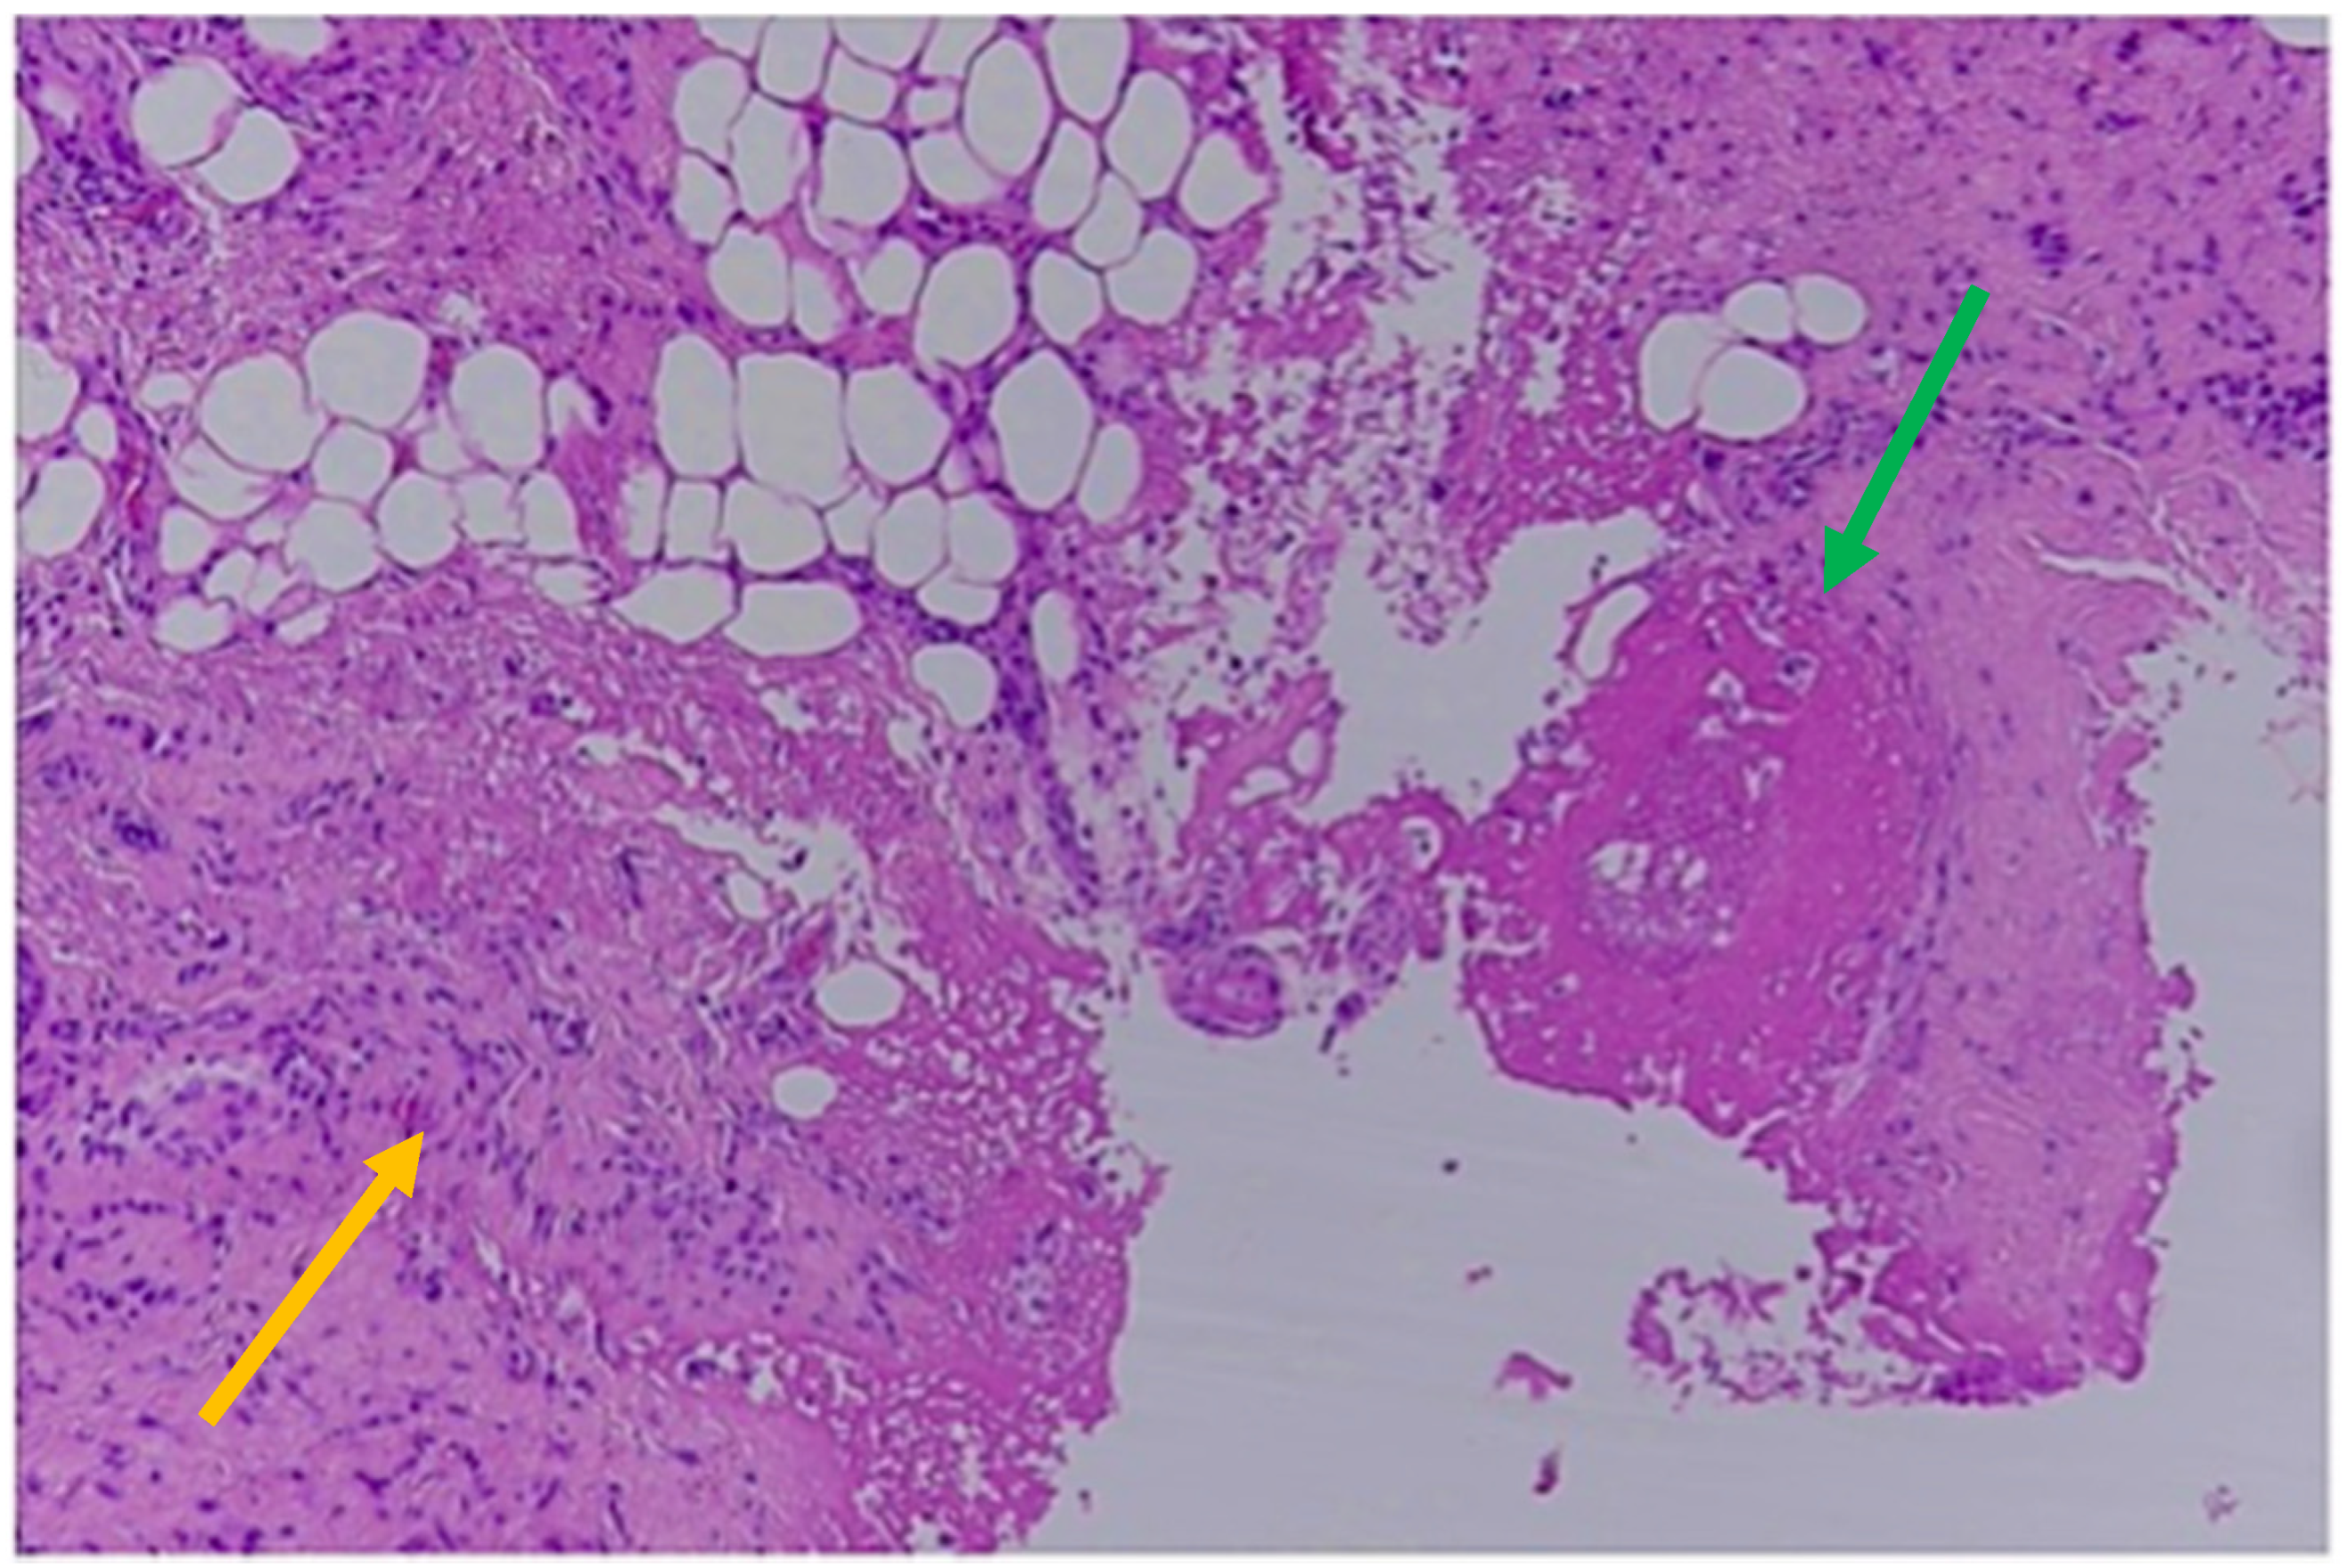

Over the sacrum there was a small area of skin loss resembling a bedsore at a very early stage. In total, 56 small bruises associated with macroscopic bleeding into the skin were detected. Bruises of different sizes were represented, mostly oval/round in shape, ranging from 0.5 cm up to 6 cm in diameter, and from red through purple to yellow/green in color. Cranial bruises were mostly located on the vertex but also on the root of the nose and on the left side of the face (in particular, at the upper eyelid, at the posterior surface of the left ear and the cheek and, finally, under the chin). Multiple contusions were also distributed in the dorsal and lateral surfaces of the upper extremities and lateral breast on both sides, consistent with forceful grasping/gripping or repeated blows. At autopsy, a frontoparietal hematoma, 4 × 3.5 cm in dimension, was associated with a bilateral subacute SDH, approximately 2 cm thick, with fresh coagulated blood between the arachnoid and dura mater. No skull fractures and no traumatic injuries of the hyoid bone were found. Unfortunately, no ophthalmic examination was performed; neither the optic nerve nor the eyes were removed at autopsy. At the neck, no hemorrhages of the soft tissue were found. The heart showed coronary atherosclerosis with mild non-obstructive plaques. Toxicological analyses were negative for alcohol and common illicit and licit drugs in peripheral blood samples as well as in hematoma blood samples. Microscopic examination of bruises and SDHs was performed using basic histological stains such as hematoxylin-eosin. The main purpose of the histological examination was to search for tissue characteristics useful for determining the age of the brain and skin injuries. In fact, although bruises cannot be aged by their color, the color may enable one to suspect whether a skin injury is fresh or not fresh, to then be confirmed by conventional histology. According to the histological examination of the scalp, face, chest and upper and lower extremities, skin samples were collected and more than 10 bruises were assessed to be older than 5 days. These were from blue/purple to yellow/green in color and were located at the face, the breast and the upper limbs. The main microscopic findings were the detection of granulation tissue with new capillary blood vessels, dense collagen fibers with fibroblasts and scar tissue and the infiltration of macrophages and lymphocytes [34]. These histological findings were observed in samples collected from the head, the face, the lateral chest of both sides and the upper extremities (Figure 3).

Figure 3.

Histological findings of 5-day-old bruises: new capillary blood vessels (green arrow); granulation tissue; infiltration of macrophages and lymphocytes (yellow arrow; Hematoxylin & Eosin).